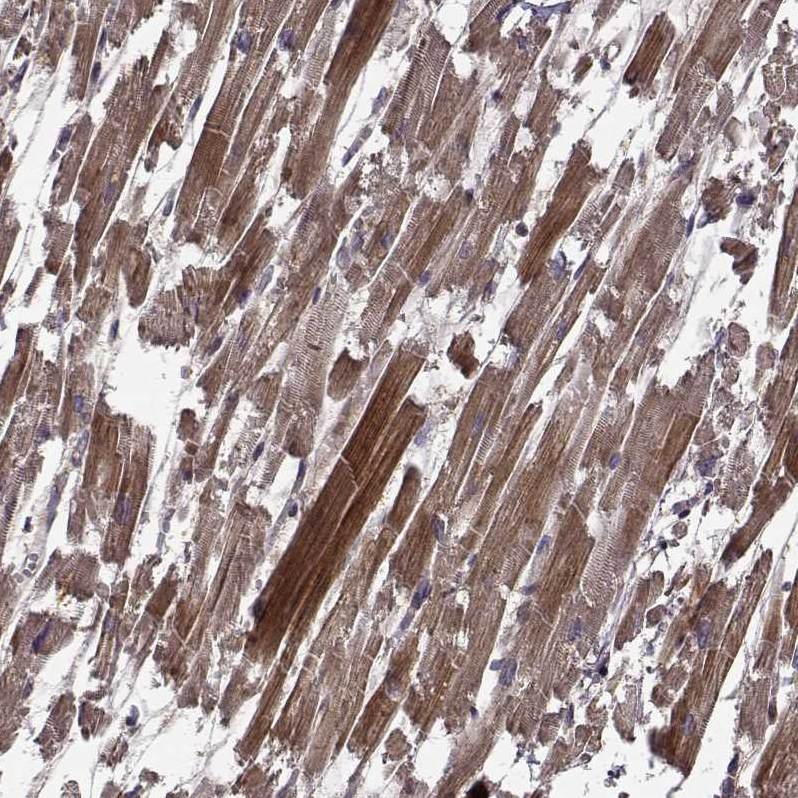

Immunohistochemical staining of human kidney shows moderate granular cytoplasmic positivity in cells in tubules.